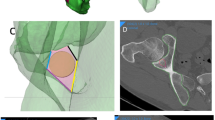

Thus, virtual screw positioning was performed by defining entry and exit point of the screw on the 3D surface models using Amira software. The overall mean model and each of the 150 individual computer models were oriented in a way allowing for a direct view into the screw corridor, described as gun barrel view25 (Fig. 2a). In a second step, orientation was adjusted so that the maximum diameter of the screw corridor was displayed (Fig. 2b). The landmarks defining entry and exit point of the virtual screw were positioned in the region of the pubic tubercle and the posterior ilium in the center of the projected corridor (Fig. 2c). Between those two landmarks, a virtual bore probe with a diameter of 7.5 mm was placed in order to simulate screw positioning. Length and local grey values of the virtual bore probe were analyzed in 1 mm steps26. The corridor’s dimensions were defined to allow screw positioning if that bore probe with a diameter of 7.5 mm would not affect surrounding cortical bone along the corridor except for the entry and exit points. Affecting cortical bone was defined by exceeding a threshold of 400 HU27,28,29. This calculation was performed on the overall mean model and on both pubic ramus of all bone models resulting in a total of 300 individual bore probes available for evaluation. In case of perforation of cortical bone, except for the entry and exit points, the screw corridor was judged as not accessible and the sample was excluded from length analysis. In all samples with an available screw corridor, screw length was measured. For further evaluation of the local bone stock, the pattern of bone stock distribution of every single sample with an available screw corridor was normalized to the average screw length and graphically visualized.

(a) Orientation of the 3D model in so-called gun barrel view25, (b) screw corridor (marked in red), (c) marked screw entry point in the center of the corridor (green dot). This figure was generated using the software Amira (Version 6.0.0, FEI, Hillsboro, OR, USA; www.fei.com).